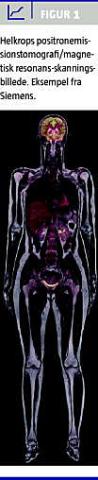

For specialet klinisk fysiologi og nuklearmedicin var det et tigerspring fremad, da den første positronemissionstomografi (PET)/magnetisk resonans (MR)-skanner blev lanceret i 2010 (Figur 1 ). Udviklingen af kombineret PET/MR-skanning har været længe ventet og er teknisk kompleks, da simultanoptagelse af PET og MR nødvendiggør, at PET-detektorerne placeres i magnetfeltet, uden at der opstår påvirkning mellem disse [1]. Takket være en stor donation fra The John and Birthe Meyer Foundation blev Nordens første PET/MR-skanner indviet på Rigshospitalet i december 2011.